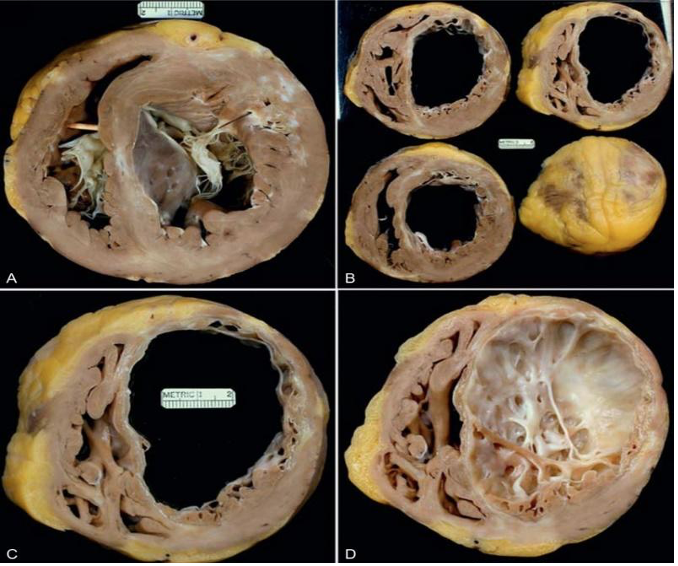

Figura 2: Cardiomiopatia isquêmica.